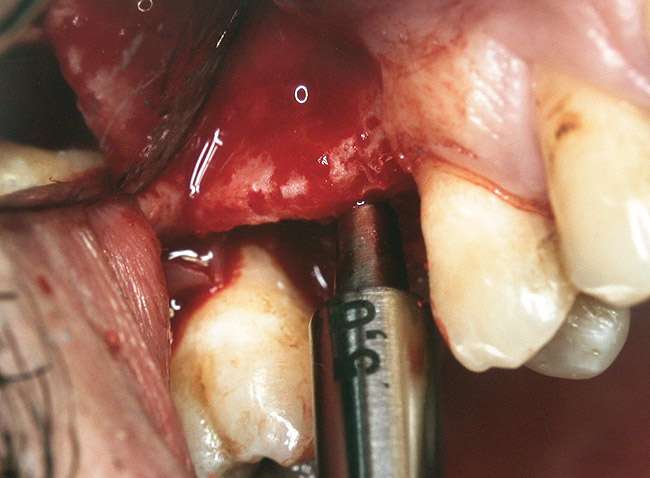

At the time of surgery, local infiltrative anesthesia was administered (lidocaine 2% with epinephrine, 1:100,000). A full-thickness mucoperiosteal flap was raised. The initial osteotomy was performed on midcrestal bone using a rose-headed bur. To prepare the osteotomy site for implant placement, sequential alternating osteotomes with variable conicity were used, drilling 2-mm shorter than the length of the implant to be placed (Figure 3A and Figure 3B). The implants presented initial primary stability (Figure 4), the cover screws were placed, and the implants were submerged for a healing period. The tissue was approximated, and the patient was instructed not to wear any denture or to place pressure on the healing site.

Figure 3A and Figure 3B Alternating osteotomes with variable conicity used to perform the alveolar remodeling in the area of tooth No. 24.

Figure 3a  Alternating osteotomes with variable conicity used to perform the alveolar remodeling in the area of tooth No. 24.

Figure 3a

Figure 3b  Alternating osteotomes with variable conicity used to perform the alveolar remodeling in the area of tooth No. 24.

Figure 3b